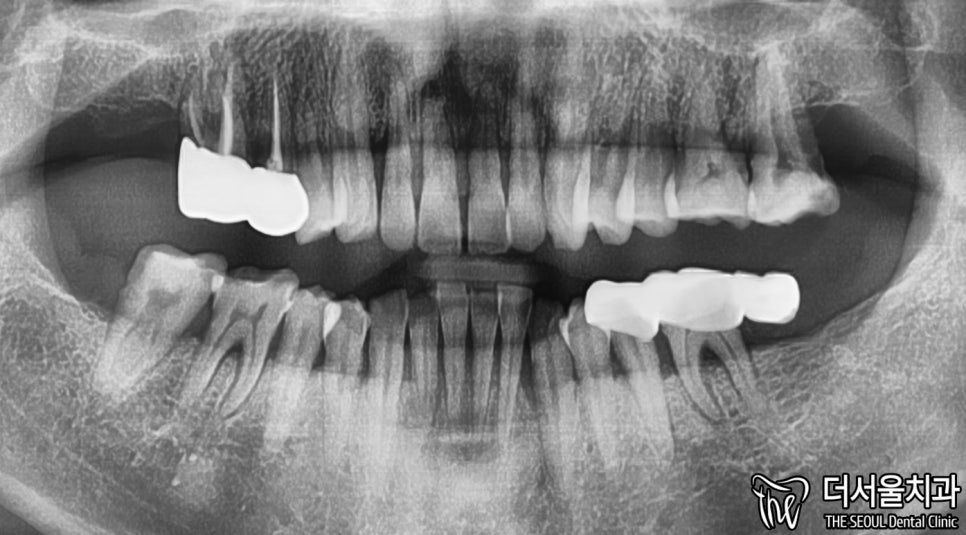

2. 엑스레이

X-ray 촬영본을 보면,

치아 뿌리에 염증이 발생한 것을

확인할 수 있습니다.

좀 더 자세히 보여드리겠습니다.

뿌리 쪽을 보면 시커멓죠?

염증이 있는 것을 알 수 있습니다.

이러니 흔들림이 나타날 수밖에 없구요.

아래 왼쪽 어금니 부분에도 마찬가집니다.

뿌리 끝은 아니지만,

중간 즈음으로 검게 변한 것을 볼 수 있습니다.

다행이었던 점은

두 곳에 나타난 염증이 그렇게 크지 않습니다.

때문에 바로 발치 후 즉시 식립이 가능합니다.